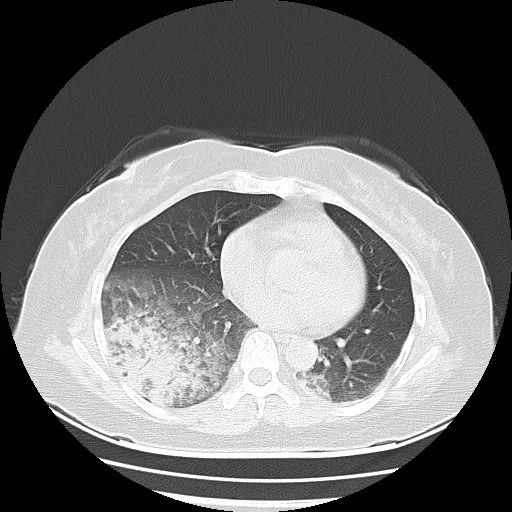

辅助检查:肺部CT:两肺下叶感染。血常规:白细胞 12.19*10^9/L↑;中性粒细胞% 78.1%;红细胞 3.95*10^12/L;血小板 391*10^9/L;C反应蛋白(超敏) 196.83mg/L↑;血沉118(0~20 )mm/h↑;肝功能:胆红素 9.2μmol/L;白蛋白 33.5g/L ↓;球蛋白 26.6g/L;谷丙转氨酶 77U/L↑;谷草转氨酶 69U/L↑;铁蛋白 624.90μg/L↑;B超:肝内囊肿,右肾囊肿,双肾结石。肺功能:轻度限制性肺通气功能障碍,小气道异常。肺炎支原体、衣原体抗体、大小便常规、隐血、肿瘤系列、肾功能、电解质、降钙素原(PCT)、ANCA系列、抗核抗体、甲状腺功能、痰培养、血培养均正常。

图1 肺部CT(20210615)

图2 肺部CT(20210615)

图3 肺部CT(20210615)

治疗过程:患者诊断为“肺炎”,予“哌拉西林钠他唑巴坦钠针联合左氧氟沙星针”抗感染治疗,入院当天患者出现发热38.2℃,后持续发热,无畏寒寒战,体温波动37-38.5℃,不规则热热型。予支气管镜检查为:支气管炎症性改变。支气管肺泡灌洗液(BALF)培养:木糖氧化无色杆菌,BALF二代基因测序(NGS):虫煤假单胞菌。